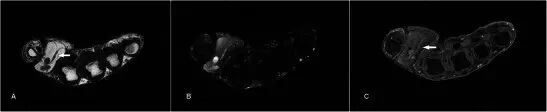

肌腱异常Tendon abnormalities 腱鞘炎是指腱和腱鞘的炎症。 局部炎症可以临床上出现质量样。 腱鞘炎的MRI发现包括腱鞘内的流体信号增加,腱鞘扩张,滑膜增殖和增强(图23)。 根据一项研究,由MRI诊断的手的屈肌腱鞘炎是早期类风湿性关节炎的强预测因子[57]。

图23.腱鞘炎在24岁女性中具有1个月的肿胀,疼痛和在左食指的屈肌方面的运动范围的损失。 (a)T1w序列显示食指的屈肌腱鞘的扩散增厚(箭头)。 (b)T2w-FS序列显示指示水肿的屈肌腱鞘的增厚和增加的信号。 (c)缓慢增强

在慢性腱病的罕见病例中,慢性炎症和腱肿胀表现为局灶性肿胀,导致骨性扇贝和钙化的条纹图案(图24)。 在这种情况下的主要鉴别诊断是GCTTS,但是MR有效地排除了基础质量损伤。

图24.慢性钙化性肌腱病变的病人呈现10年的肿块沿着左中指的手掌方面的病史(a)平片显示沿着中指手指近指节的手掌方面具有良好定义的扇形,具有上覆的条纹图案 的钙化(箭头)。 (b)T1w序列显示屈肌腱长肌腱(箭头)的灶性肿胀引起下面的骨的扇贝。 没有看到离散质量。 (c)在T2-FS序列上的腱中存在轻度增加的信号,表明肌腱炎。 有骨性扇贝,但没有显着的骨髓水肿,暗示一个慢性过程。 (d)看到腱鞘的扩散增厚和强烈增强,反映活动性腱鞘炎(箭头)